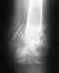

А теперь главное. У меня открытый оскольчатый перелом правой бедренной кости. Собрали мне ногу в 36 больнице, поставили аппарат Илизарова. На снимках четко видно, что кость которая идет от колена наложена на кость которая идет от бедра, и в области перелома на костях есть трещины. Вопрос: Срастется в таком состоянии бедренная кость и сколько времени нужно для сращивания? Заранее благодарна за Ваш ответ.

Хорошо бы увидеть рентгеновские снимки всего бедра на протяжении (и фас, и профиль). А что говорит врач в 36 ГБ? Не собираются что-то аппаратом делать? Восстанавливать длину, ось?